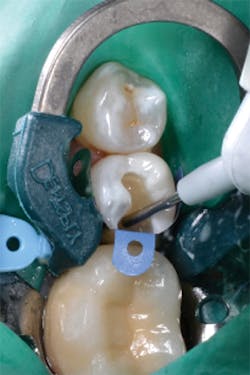

Figure 12: Final preparations on teeth Nos. 4 and 5. The Palodent Plus Sectional Matrix System has been used to isolate the MOD prep on tooth No. 4 and MO prep on tooth No. 5. The Palodent Plus Sectional Matrix System can be configured to restore multiple surfaces and multiple teeth in the same quadrant.

Figure 13: View of teeth Nos. 4 and 5 after curing the final occlusal layer of TPH Spectra composite.